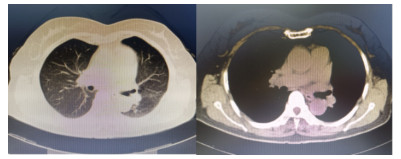

1 资料与方法患者,女,64岁,居住农村,既往有糖耐量异常5年,未正规治疗,4年前诊断为“原发性甲状腺功能亢进”,经治疗已好转。无高风险、中风险地区旅居史,无境外旅居史,无新冠病毒肺炎确诊或疑似患者接触史。2020年7月31日患者无明显诱因下在家中出现发热,体温最高39.4 ℃,伴畏寒、全身乏力,无胸闷、胸痛,无咳嗽、咳痰,无腹痛、腹泻,无黑矇、晕厥,遂在家中自服“退热药”后体温降至正常,但体温仍有反复。8月2日早晨患者再次出现发热,伴畏寒、寒战,遂至本院发热门诊就诊,予查C-反应蛋白156 mg/L,降钙素原0.64 ng/L,考虑感染性发热,遂予“哌拉西林他唑巴坦钠4.5 g每12 h一次”静滴抗感染治疗,后患者突发呼吸费力,伴咳嗽、咯血,为鲜红色血液,量较多,遂于8月2日14:18送达本院急诊抢救室。来时患者呼吸急促,有咳嗽伴咳血性痰,双侧小腿持续性钝痛,查体:血压188/86 mmHg(1 mmHg=0.133 kPa),心率168次/min,呼吸36次/min,血氧饱和度50%,体温38.6 ℃。神志清,精神软,急性面容,双侧结膜略充血,全身皮肤黏膜未见明显充血、淤血,未触及淋巴结肿大。口唇微绀,两肺呼吸音粗,可闻及明显湿性啰音,心律齐,无明显病理性杂音;腹平软,无压痛反跳痛,四肢肌力Ⅴ级,两侧病理征未引出。予心电监护、特级护理、面罩吸氧、建立静脉通道,送检血常规、生化、血气、心肌酶、凝血酶原时间系列、痰培养等常规检查,同时予送检血标本行高通量测序,完善胸部CT检查(图 1)。辅助检查结果如下:8月2日胸腹部CT示两肺感染,腹部未见明显异常。血常规:白细胞计数7.9×109/L,中性粒细胞百分比89%,血红蛋白121 g/L,血小板计数104×109/L,C-反应蛋白156.82 mg/L。血生化:丙氨酸氨基转移酶51 U/L,天门冬氨酸氨基转移酶63 U/L,白蛋白34.5 g/L,总胆红素17.4 mmol/L,肌酐74 mol/L。心肌酶谱:心肌肌钙蛋白I 0.014 ng/mL,肌红蛋白322 ng/mL,肌酸激酶同工酶3.2 ng/mL。血气分析:pH 7.435,二氧化碳分压29 mmHg,氧分压53.5 mmHg,K+ 2.6 mmol/L,Na+ 132 mmol/L,血乳酸3.1 mmol/L。新型冠状病毒抗体、核酸阴性。接诊医师初步诊断为“咯血待查:疑似肺部感染,呼吸衰竭”,治疗上予亚胺培南0.5 g静滴经验性抗感染、甲泼尼龙80 mg静滴抗炎,同时予化痰、平喘等对症、支持。17:00患者出现呼吸费力加重,10 L/min面罩吸氧下血氧饱和度仍为70%,故予紧急气管插管、机械通气,随后转入ICU,联系感染科医师会诊,结合患者病史及CT影像学表现的广泛、片状密度增高影特点,考虑钩端螺旋体病可能性大,不排除“赫氏反应”,故继续予亚胺培南0.5 g静滴每6 h一次抗感染、甲泼尼龙80 mg静滴每12 h一次抗炎、白蛋白营养支持等治疗。8月3日更改甲泼尼龙80 mg静滴每天一次。8月4日高通基因测序回报:检测出问号钩端螺旋体DNA,符合入院时推断,明确病原体后予修正诊断为肺出血型钩体病伴赫氏反应。8月5日停亚胺培南,改青霉素160万单位静滴每8 h一次。8月8日患者病情稳定,拔除气管导管,予甲泼尼龙减量为40 mg静滴1次/d,8月9日复查胸部CT提示两肺斑片状、片状密度增高影较前有所吸收(图 2),停用甲泼尼龙。8月10日转入呼吸科。8月17日复查胸部CT提示两肺斑片状、片状、条索状密度增高影,较前明显吸收(图 3)。8月20日患者好转出院。9月18日随访,复查CT提示两肺散在条索状密度增高影,基本恢复正常(图 4)。

| 图 2 8月9日胸部CT示两肺斑片状、片状密度增高影较前有所吸收 |